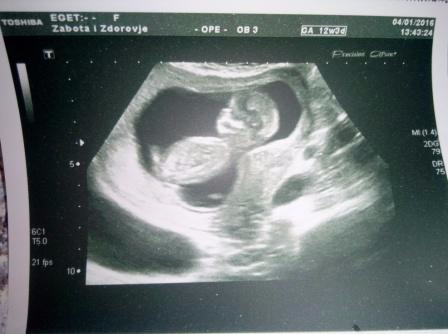

4.01. мы повторили узи,за 2 недели малыши подросли чуть ли не в 2 раза(с 37 и 38мм до 62 и 60мм).Развиваются согласно сроку,сердечки бьются в унисон 158 уд\мин. Проверили наличие хромосомных аномалий-оба малыша абсолютно здоровы,чему мы были несказанно счастливы.Теперь совместных фоток уже не получилось сделать,теперь каждый отдельно)))Матка расположена правильно,тонуса и угрозы нет,но мы все равно сбавили обороты нашей интимной жизни.

ну и фоточки моих любимых